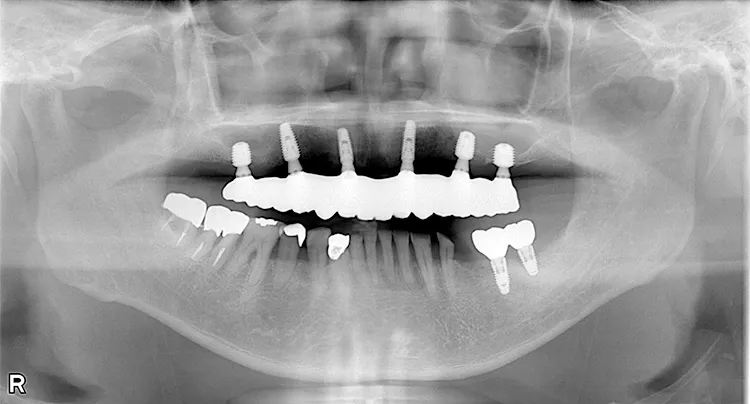

歯ぎしり・食いしばりが強い方の治療ケースです。全体的に歯が擦り減り正面から見て下の歯が見えないほど噛み合わせの高さが失われており、顎関節にも症状がでていました。ヒビが入って保存不可の歯を抜歯しインプラントを計5本埋入し、前歯・臼歯にインプラント土台のブリッジを入れることで噛み合わせの高さを回復しました。古い金属の被せ物もジルコニアでやりかえました。噛み合わせの高さが改善したことで顎関節症状もなくなり快適に過ごされています。歯ぎしりがある方は、夜間のナイトガード装着が必要になります。